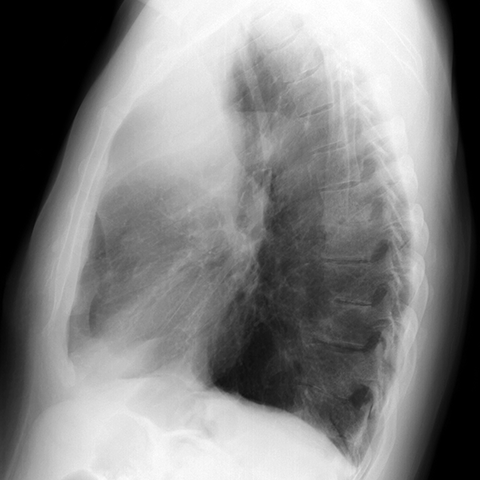

RUL Atelectasis, Consolidation and Cancer [2 of 3]